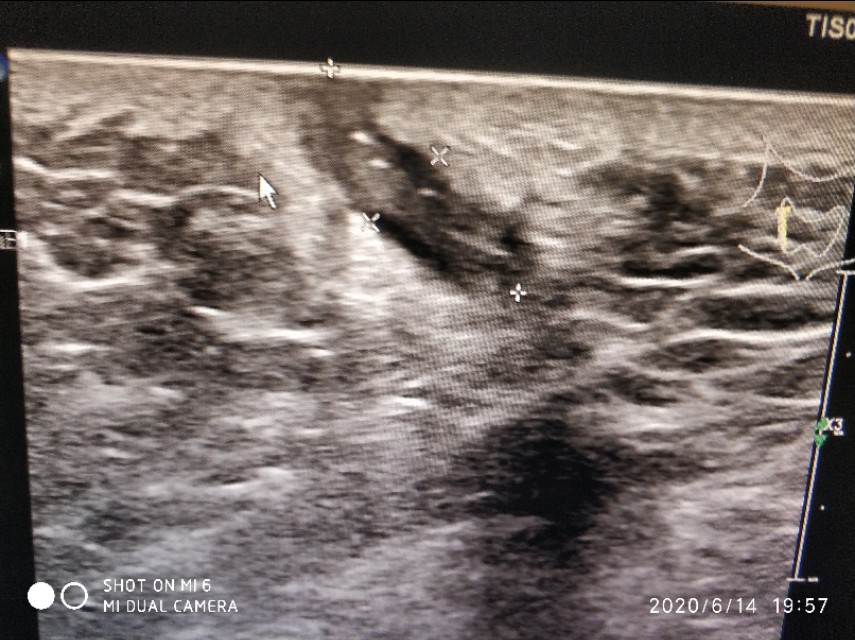

这是一个藏毛疾病的患者,不过这是一例手术后复发的病人,长得像一个小尾巴一样,里面可以见条状的线状稍高回声。我在丁香园里特别找了几幅手术中的照片,非常的难以入目,真的是少儿不宜。治疗方法一般是切开引流,还有切开一个菱形的口子,把里面一些坏死的组织挖出来。